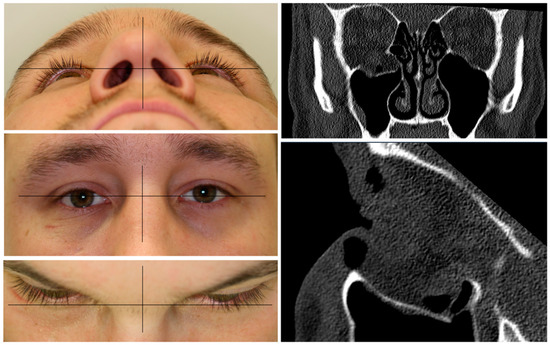

A patient with an orbital floor fracture due to a fall was in need of primary orbital reconstruction. He suffered from binocular double-vision, hypesthesia of the right infraorbital nerve, and a hypoglobe with slight enophthalmos on the affected right side (see Figure 1). The CT data showed a defect size of 17.9 mm in the coronal plane and 23.4 mm in the sagittal plane. Due to the defect size, the mode of reconstruction was chosen as an alloplastic reconstruction with a titanium mesh. To show the different fitting qualities, a pre-fabricated titanium mesh was compared to a PSI.

Figure 1.

Clinical photographs of the patient showing an enophthalmos in the perspective from below and above, with a hypoglobe present on the right affected side as visible in the frontal view. The coronal and sagittal planes of the pre-operative CT scan displaying the traumatic defect of the orbital floor on the right side.